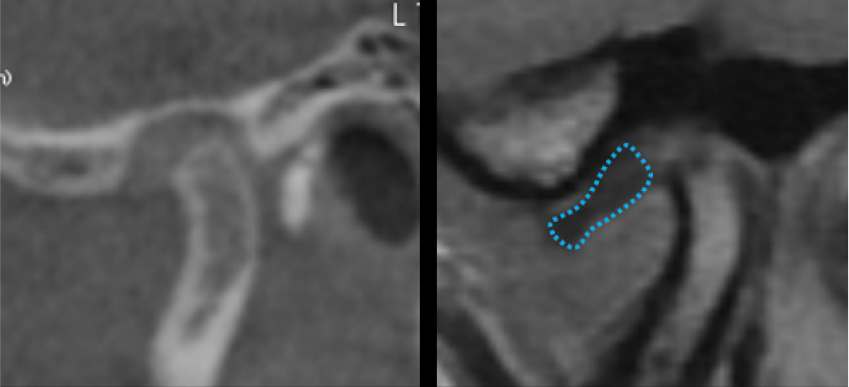

As previously mentioned, disk displacement can cause degenerative changes or hinder normal growth. Magnetic resonance imaging is the standard of care for assessing the position and condition of the disk and for detecting early signs of TM joint dysfunction; however, MRI availability can be limited. Cone-beam computed tomography has become more accessible in dentistry and can act as a guide for TMJ stability.

CBCT is ideal for evaluating osseous structures. The size and shape of the condyle and the intraarticular space can be assessed in conjunction with a comprehensive TM joint examination, providing insight into the position of the articular disk. In both adults and growing individuals, the condyle should take up about 66% of the glenoid fossa. If the condyle is not proportionate to the glenoid fossa, it may indicate an early growth disturbance, condylar breakdown, or a combination of both.

While the size and shape of the condyle indicate whether there was a growth disturbance or osseous breakdown, the space around the condyle in the glenoid fossa can serve as a screening tool to help determine if magnetic resonance imaging is necessary. A disk displacement can shift the condyle within the fossa, leading to changes in the space.

The articular disk is a biconcave structure that’s thicker on the anterior and posterior aspects, with a thinner avascular central bearing zone. The central bearing zone is typically 2–3 mm thick and functions to distribute the load between the condyle and the glenoid fossa. When the disk is properly positioned, the posterior band wraps around the back side of the condyle, positioning it in a concentric location (Fig. 4a). When a disk herniates, it can cause a deflection of the condyle, disrupting the joint space and providing insight into the disk’s position (Fig. 4b).